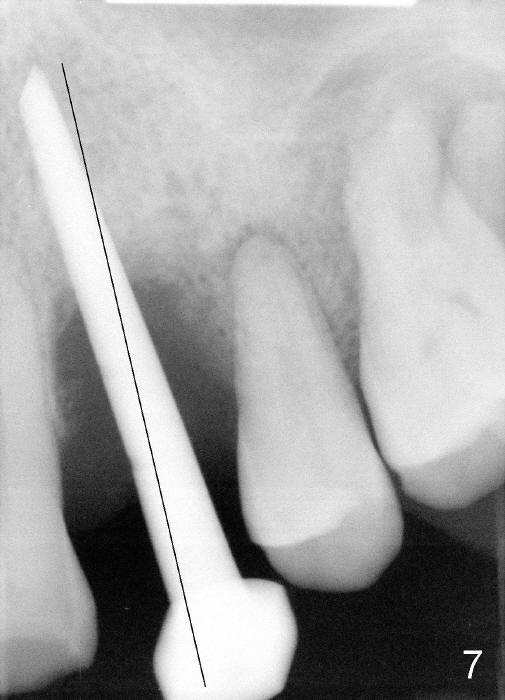

Dear Drs. Dunson and Borgner: Thank you for support. Fig.5 and 6 taken immediately prior to surgery show that the healing socket is elliptical (arrowhead). After D1 and D2 channel formers, D2 thin socket former is tapped in (Fig.7). The osteotomy needs to be redirected as shown by the black line. D2 implant is being inserted with Synthograft applied to the 1st two threads (Fig.8) and is in place (Fig.9,10). But the implant is not as stable as expected. There is a gap mesial to the implant (Fig.10 arrowhead), which is most likely created by re-directing the osteotomy with channel and socket formers.